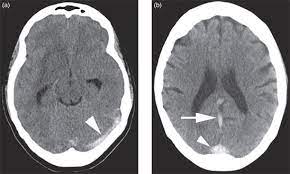

Cerebral venous sinus density on noncontrast ct correlates with hematocrit. Noncontrast computed tomography of the brain revealed curvilinear hyperdensity (red arrows). Aha scientific statements ⅲ venous thrombosis ⅲ sinus thrombosis, intracranial ⅲ brain infarction figure 1. See that article for a discussion of that specific clinical entity. Cerebral venous sinus thrombosis in children:

Common subtypes include transverse sinus thrombosis and superior sagittal sinus. What causes cerebral venous sinus thrombosis? Cerebral venous sinus thrombosis occurs when a blood clot forms in the brain's venous sinuses. Cerebral venous thrombosis (cvt) is an uncommon disorder in the general population. (iii) clinical and radiological features of brain lesions in csvt compared with arterial stroke, and (iv) a low threshold for ct or mr venography in children with acute neurological symptoms is essential.

Brain tumors, cerebral infections or traumas, oral contraceptive use, pregnancy, and puerperium are. Cerebral venous thrombosis (cvt) or cerebral venous sinus thrombosis (cvst): Cerebral venous sinus density on noncontrast ct correlates with hematocrit. Cerebral venous thrombosis (cvt) is an uncommon disorder in the general population. Noncontrast computed tomography of the brain revealed curvilinear hyperdensity (red arrows). Cerebral venous and sinus thrombosis (cvst) is a rare disease responsible for less than 1% from the total of avc causes (bajenaru, 2010). The venous circulation of the brain is done. A statement for healthcare professionals from the american heart association/american stroke association.